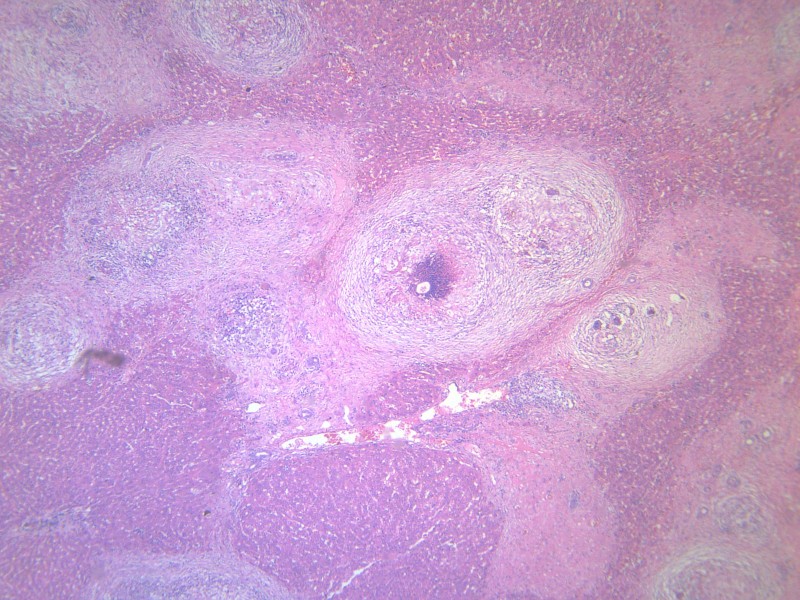

科普:肉瘤是一种“小众”肿瘤,发病率仅占所有恶性肿瘤的1%,子宫平滑肌肉瘤是子宫恶性间叶性肿瘤,占所有恶性间叶性肿瘤的25%,占所有子宫恶性肿瘤的1%,属高度恶性肿瘤,呈浸润性生长,易复发和转移,肺和肝是常见的转移部位,淋巴结和卵巢转移不常见。

2015年8月,她因一场小病“月经量明显增多”前往当地医院和天津某大医院做了子宫全切术,然而,接下来的病理结果让她和老伴儿大吃一惊:子宫平滑肌肉瘤,侵及全层子宫。

2018年11月,停化疗2年9个月,再次出现不规则阴道流血,原来治疗的北京某院检查告知复发:梭形细胞恶性肿瘤伴坏死,考虑为平滑肌肉瘤;随后分别做了3周期顺铂+表柔比星方案化疗。可是,噩梦并未结束。2019年6月份,医院复查显示:盆腔软组织肿块,约8.7cm*8.9cm*11.0cm,在医院的多学科会诊后,医生给出的答案是“没办法治了”。